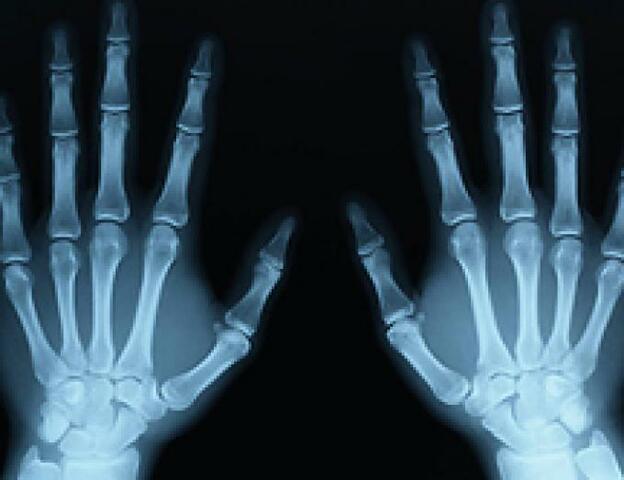

En 1895 fue el descubrimiento de los rayos X, por Wilhelm Conrad Röntgen (1845-1923), científico alemán descubrió una radiación (de origen desconocido en aquel momento, y de ahí su nombre de rayos X) que tenía la propiedad de penetrar los cuerpos opacos.

EL 23 de enero de 1896 Roentgen realizó su primera demostración de los rayos X , ante la sociedad Médica Física de Wurzburg